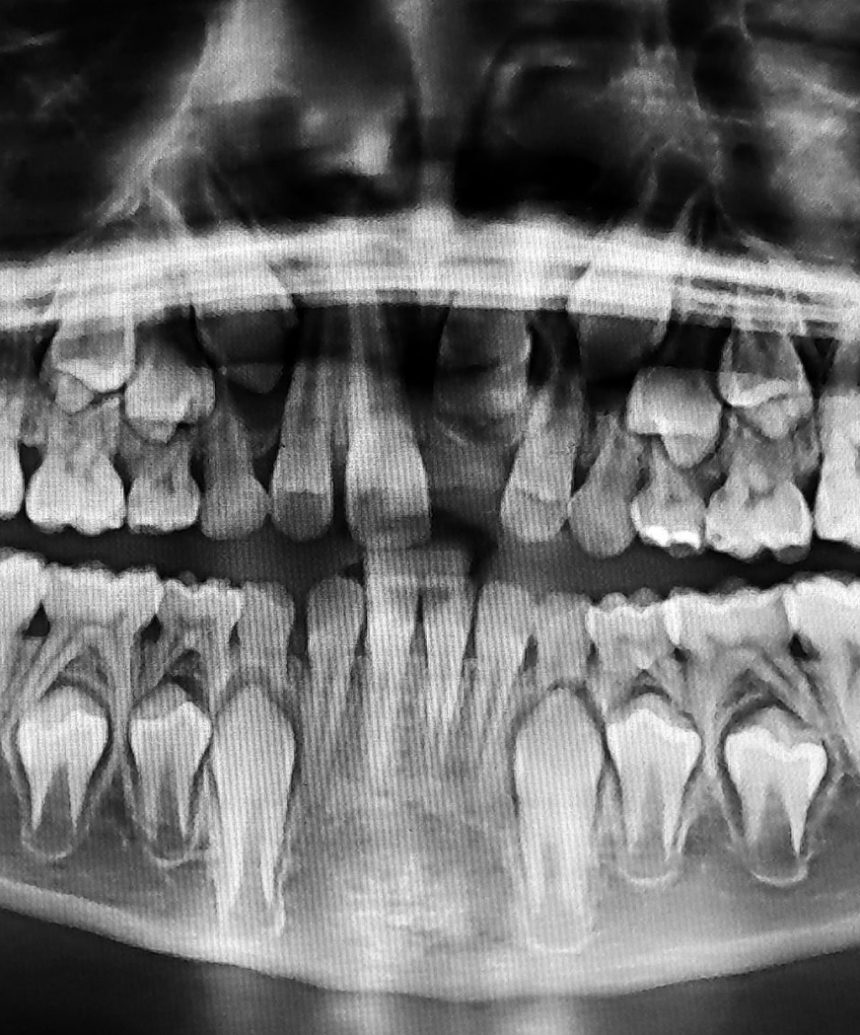

Maxilofacial

Odontología